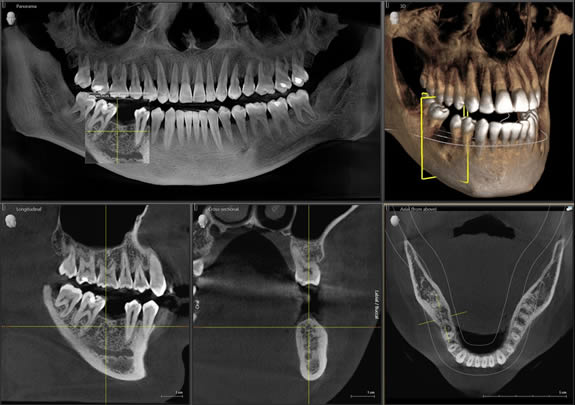

At Apex we have been investing in offering our patients the very best. We are able to offer patients, when clinically required, 3D dental cone beam (CT) imaging which enables us to plan treatment for our patients through 3-D visualisation of the jaw and teeth with outstanding and reliable images.

A 3- D dental CBCT assists with accurate placement of dental implants by accurately defining the location of anatomical structures as well as calculating the width, depth and density of the jaw bone. It also shows the pathway of nerve canals in a 3D view within an accuracy of 0.1mm, which assists with implant placements as well as removal of teeth in Oral Surgery.